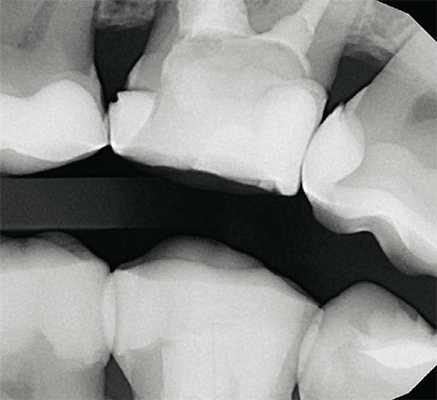

(Слева) На рентгенограмме с ПФ определяется рецидивирующий кариес под дистальной пломбой первою моляра нижней челюсти слева. Прилежащая кариозная полость напоминает треугольник, вершина которого направлена к ДЭС. Кариес распространяется вдоль ДЭС, образуя в дентине треугольное просветление с широким основанием.

(Справа) На рентгенограмме с использованием ПФ у пациента со смешанным прикусом определяются множественные проксимальные кариозные поражения. Кариес временных зубов поражает эмаль и дентин тем быстрее, чем шире волокна и канальцы в зубе. (Слева) На рентгенограмме с ПФ определяется классическая картина проксимального кариеса: поражение эмали в виде треуюльника, основание которого обращено к поверхности, а вершина к ДЭС, и треуюльное поражение в дентине с основанием, прилежащим к ДЭС, и вершиной, направленной к пульпе.